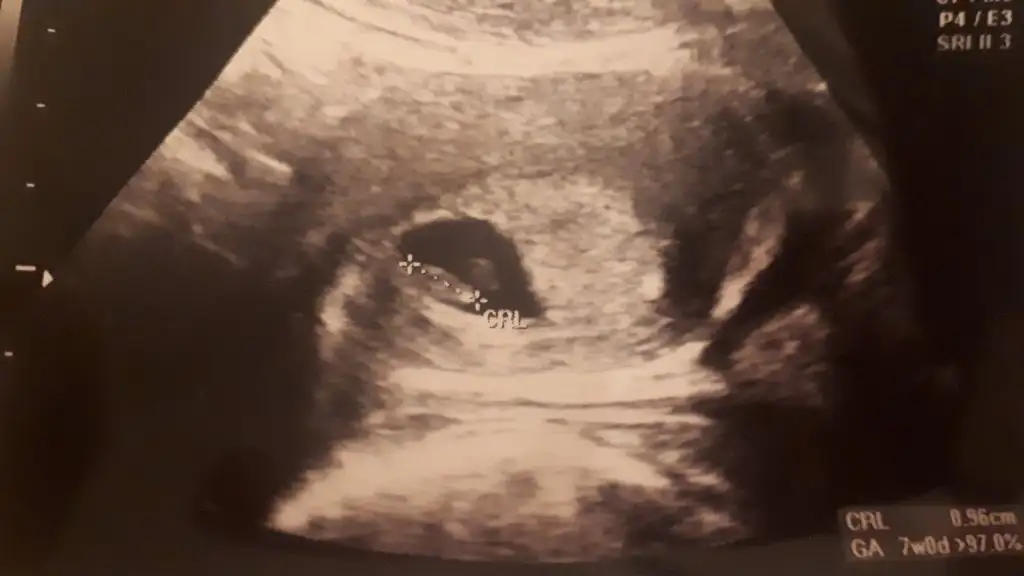

Yaaa ne kadar güzel ☺️❤️ ultrason görüntüsü nasıldı peki. Sadece yolk mu gördünüz yoksa bebeği mi gördünüz? Ben de cuma gidicem kalp atışı dinlemeye ve çok heyecanlıyım

Bebegi kesesini yolku hepsini gorduk kalp atisini dinledik insallah sende cuma hepsini gorursun resmini ekliyorum😊🙏😇

Eklentiler

• 1679159083345130476017953338374.webp

15,5 KB · Görüntüleme: 85